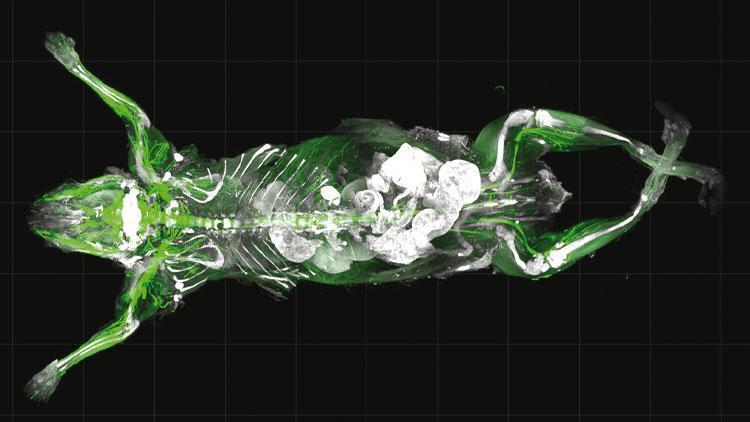

Almanya’daki Ludwig Maximilian Üniversitesi’nde (LBU) laboratuvar çalışmaları yapan nörolog Dr. Ali Ertürk ‘vDISCO’ ismini verdiği patentli metodu ile fare vücudunu saydam ve plastik kadar sert bir hale getirmeyi başardı. Bu sayede bunama, felç, şeker ve kanser gibi hastalıkların mikroskop altındaki incelemesi daha detaylı yapılabilecek, tedavi metotları geliştirilebilecek.

BİLKENT Üniversitesi mezunu olan Dr. Ali Ertürk, DISCO şeffaflığı (DISCO Transparency) adını verdiği çalışmasını bu ay ABD’nin San Diego şehrindeki ‘Nörolog Derneği’ toplantısında sundu. Büyük ses getiren teknoloji ‘Nature dergisi’ başta olmak üzere pek çok bilim dergisinde yayınlandı. LMU’daki ‘Felç ve Bunama Araştırma Enstitüsü’nde grup lideri olan Dr. Ali Ertürk, bunama, felç, şeker ve kanser gibi yıkıcı hastalıkların tedavisine yardımcı olmak için geliştirdiği yöntemle, ölü farenin vücudunu tamamen şeffaf hale getirerek hücrelerin birbiriyle nasıl bir iletişim içinde olduğuna dair anatomik sırları açığa çıkarıyor. Bu metot sayesinde canlıların, yaralanmaya ya da hastalıklara nasıl tepki verdiğinin daha iyi anlaşılacağı ve tedavi yolunun açılacağı belirtiliyor.

Dr. Ali Ertürk çalışmasını Hürriyet’e şöyle anlattı: “Kanser gibi hastalıklar, mikroskobun altındaki ince bölümlemede teşhis edilmiş ve araştırılmış olmasına rağmen önemli detayları kaçırabilmekte. Bizim teknolojilerimiz tüm örneklemi bütünüyle görmemize ve bölümlemesiz dahili anormallikleri tanımlamamıza izin veriyor. Bunu, adeta sütü suya dönüştürür gibi şeffaflaştırarak gerçekleştiriyoruz. Nörolojik hastalıkların çoğu aslında tüm vücudu etkilemesine rağmen şimdiye kadar beyin bilimcileri sadece hasarlı beyin bölgelerine odaklandı.”

BİLİNMEYEN KANALLARI KEŞFE YARDIMCI OLUYOR

Dr. Ali Ertürk: Şeffaflık teknolojimizi kullanarak, daha büyük resmi inceleyebiliriz, yani bir felç lezyonu veya Alzheimer hastalığının tüm vücuttaki nöronları nasıl etkilediği, kafatası ve beyin arasında hücre ve molekülleri taşıyan bilinmeyen kanalları keşfetmemize yardımcı oluyor. Laboratuvarda tüm insan beynini şeffaflaştırdık. Bu sayede birkaç yıl içinde insan beyninin tek parça haritalaması gerçekleşecek. 25 yıl içinde de tüm hastalıkların tedavisi mümkün olacak.